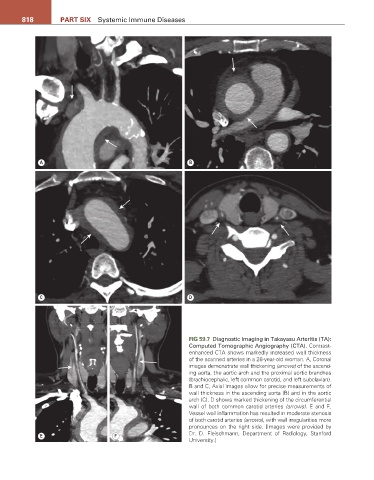

FIG 59.7 Diagnostic Imaging in Takayasu Arteritis (TA):

Computed Tomographic Angiography (CTA). Contrast-

enhanced CTA shows markedly increased wall thickness

of the scanned arteries in a 28-year-old woman. A, Coronal

images demonstrate wall thickening (arrows) of the ascend-

ing aorta, the aortic arch and the proximal aortic branches

(brachiocephalic, left common carotid, and left subclavian).

B and C, Axial images allow for precise measurements of

wall thickness in the ascending aorta (B) and in the aortic

arch (C). D shows marked thickening of the circumferential

wall of both common carotid arteries (arrows). E and F,

Vessel wall inflammation has resulted in moderate stenosis

of both carotid arteries (arrows), with wall irregularities more

pronounces on the right side. [Images were provided by

E F Dr. D. Fleischmann, Department of Radiology, Stanford

University.]